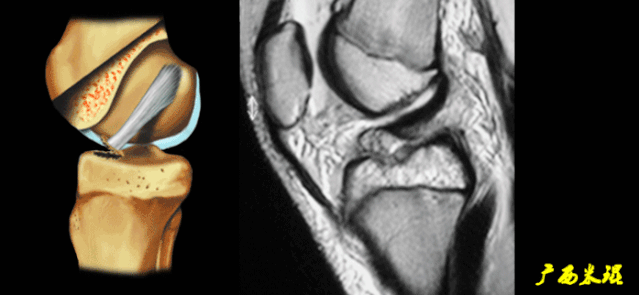

(二)ACL的正常MRI表现

各序列均为低信号。

韧带平直,边界清楚,有较好的张力。

韧带内可有脂肪及滑膜条纹影。

(四)ACL最好的观察层面

最好的观察层面是斜矢状面。

必须结合横断面和冠状面。

(五)ACL角度

矢状面ACL与髁间窝的顶部形成一个13°的夹角。